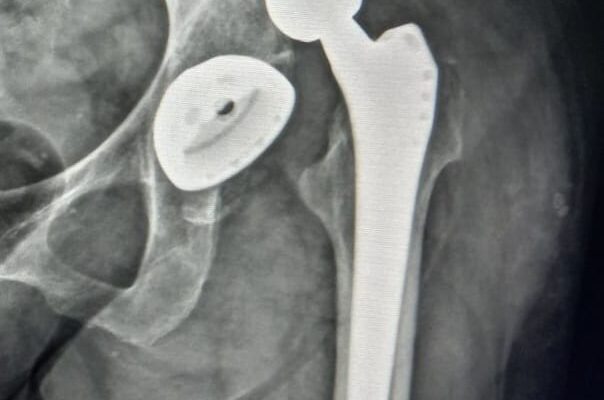

Що не можна робити після ендопротезування

Після ендопротезування важливо знати, що не можна робити, щоб уникнути ускладнень і забезпечити успішне відновлення. Існують певні дії, яких краще уникати, щоб новий штучний суглоб служив довго і без проблем.